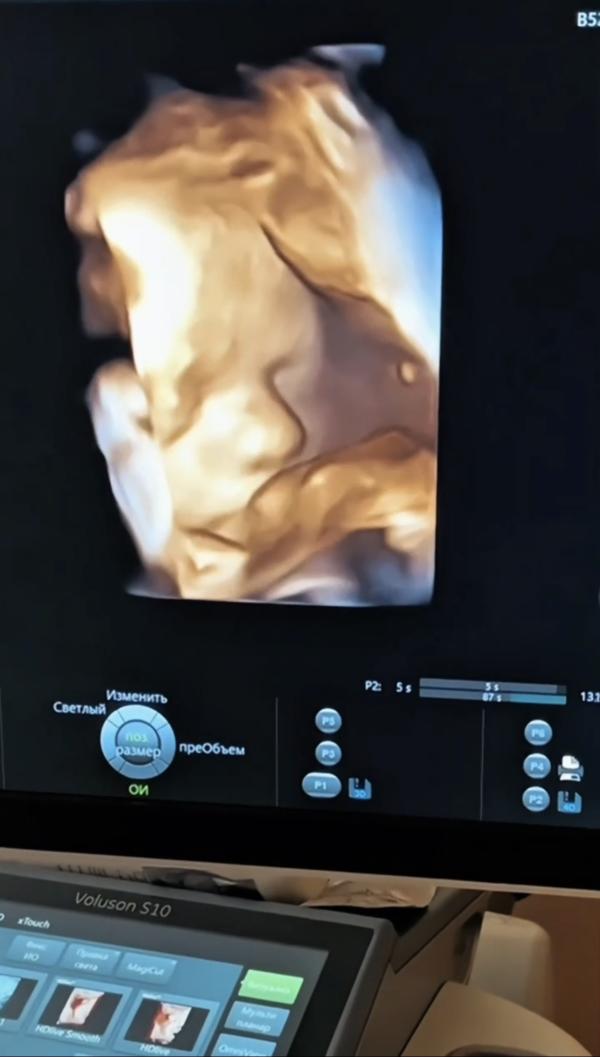

@mi742a, вообще очень похож 😍 ещё язык показал ! Вот же проказник 😄

@balybina42, ну вот на 24 неделе ходили

и черты лица уже рассмотрели и даже улыбнулся нам на видео 😅